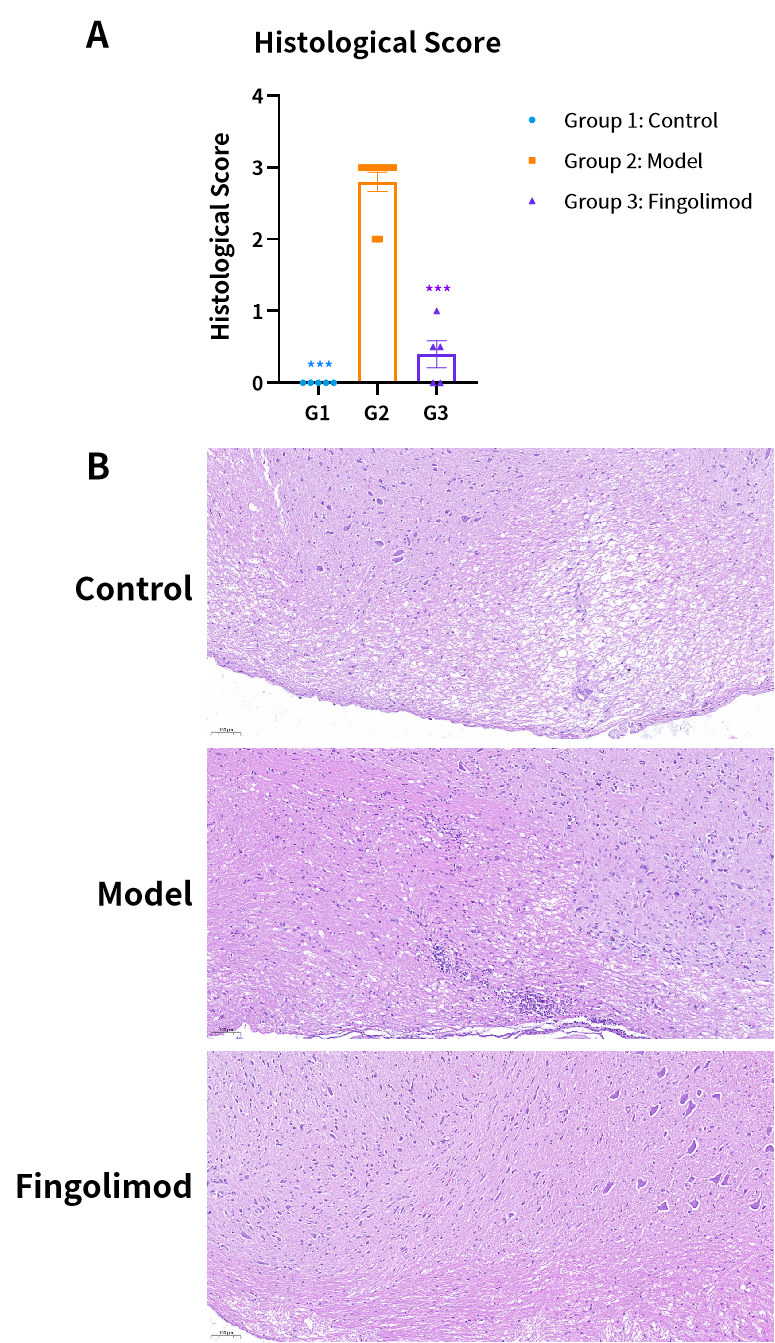

Fig2. MBP诱导EAE模型典型病理染色结果及组织学评分。

在注射抗原后,定期对动物进行临床评分,监测其行为和运动障碍。评分系统通常包括对瘫痪严重程度的评估。组织学评估

在实验结束时,通过组织学方法(如HE染色、LFB染色)检查动物中枢神经系统的炎症和脱髓鞘情况。